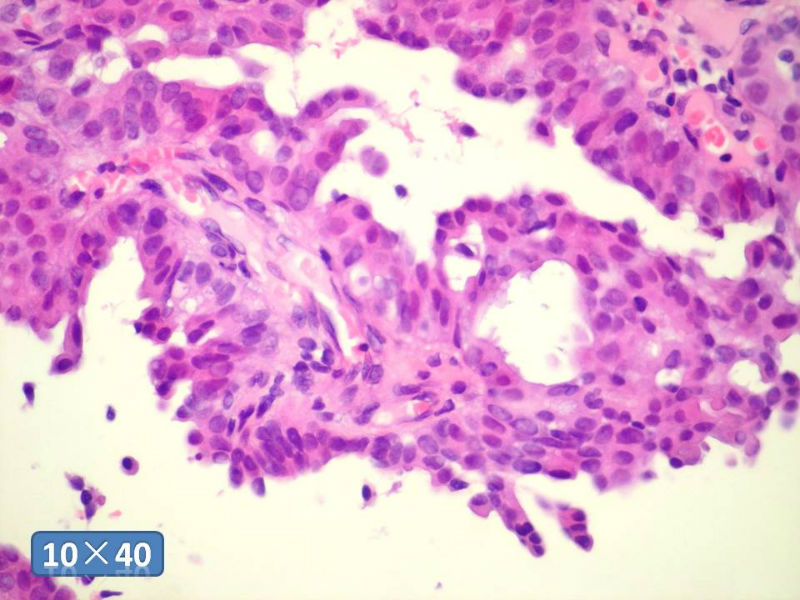

只能说是乳头状瘤

是不是导管内

乳头状瘤 and 导管内乳头状瘤 are the same; Benign lesion.

After you work up and you still cannot be sure it is benign , atypical or maignant lesion, you can call 乳头状lesion.

If this is excisonal case, you should figure out the nature of the papillary lesion.

我的意思就是提醒大家 在不是很确定的情况下 尽量少给自己套枷锁